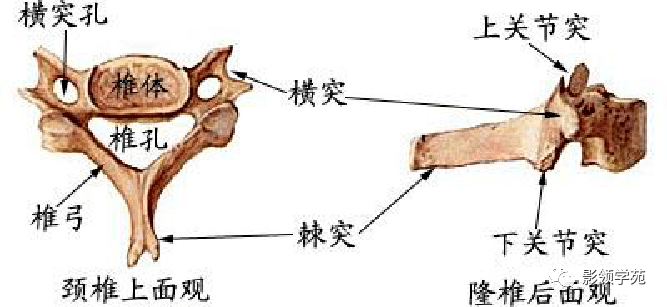

骨骼系统

骨骼系统